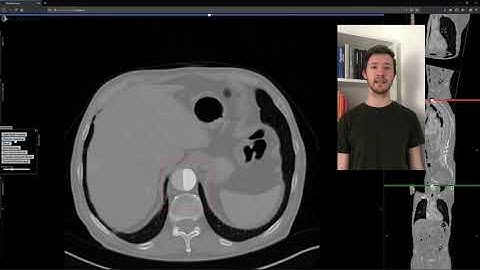

Semi-supervised Virtual Regression of Aortic Dissections Using 3D Generative Inpainting (Talk)